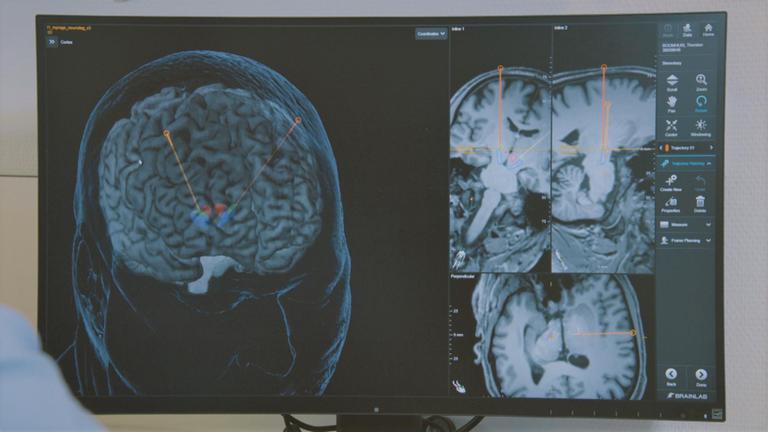

4. Gehirnscan auf Computer spiegelt sich in Brille

Hohe Dunkelziffer:Stummer Schlaganfall meist zufällig entdeckt

von Silke Potthoff

mit Video